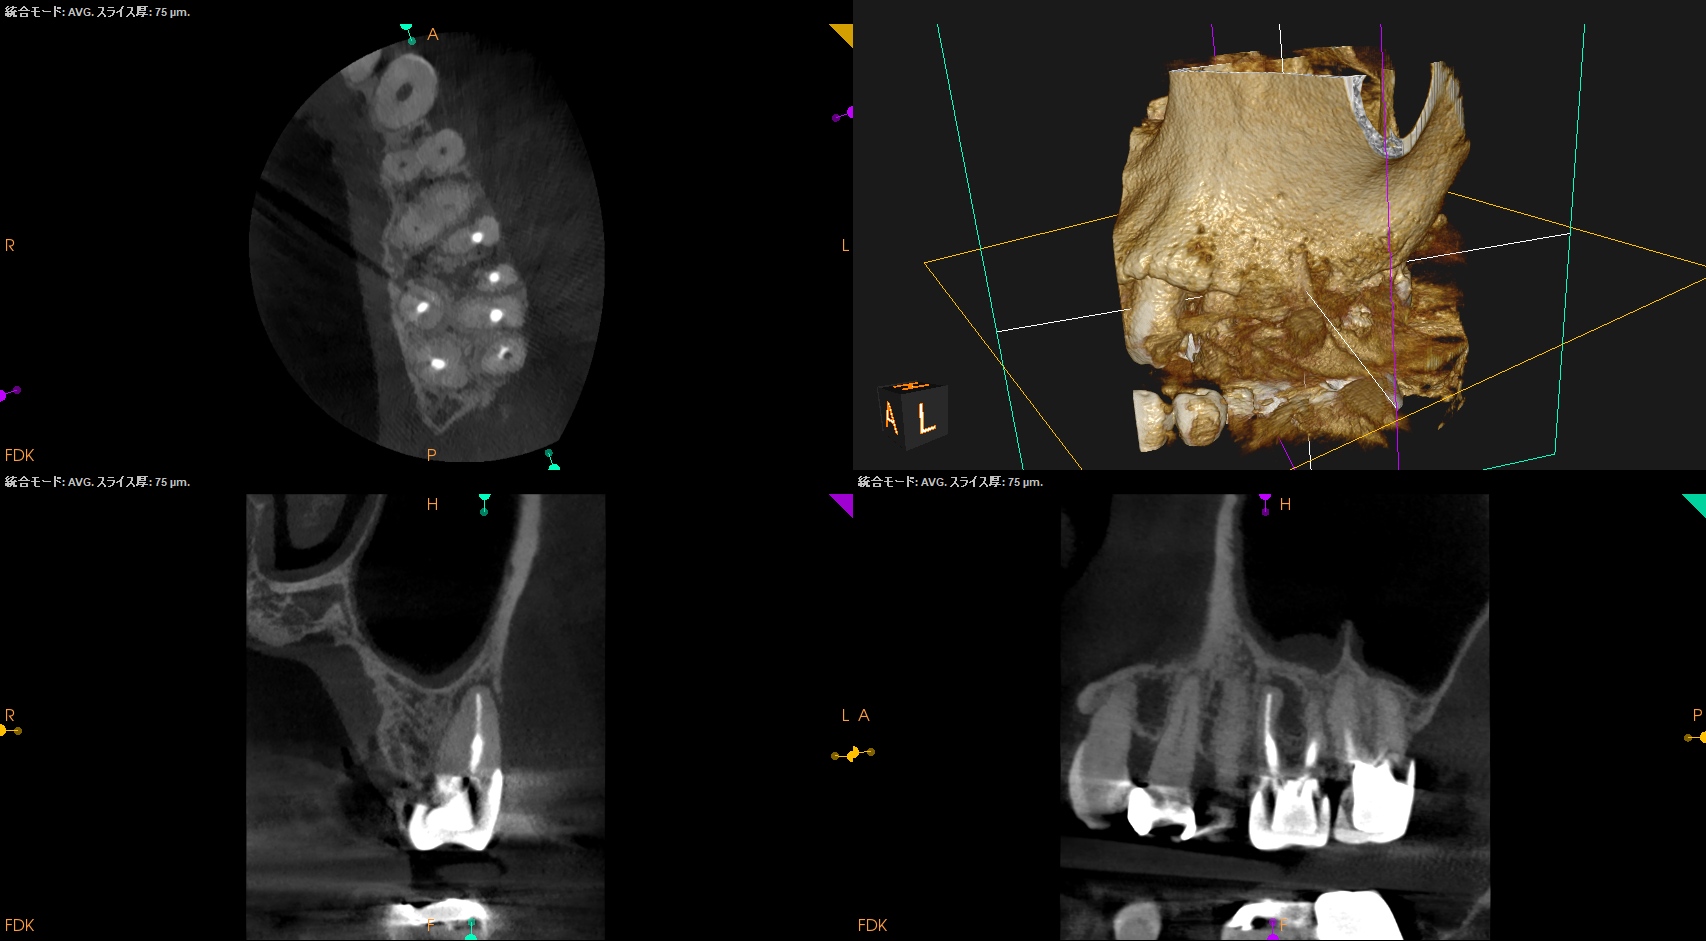

画像はどうだろうか?

MBの歯根周囲に病変がある。

MBの根管口部もいかにもピーソーリーマーで掘りましたよ、とVRFを惹起させる可能性が高い状況証拠まで存在する。

そしてそこに歯周ポケットが8mm…

VRFが濃厚かもしれない。